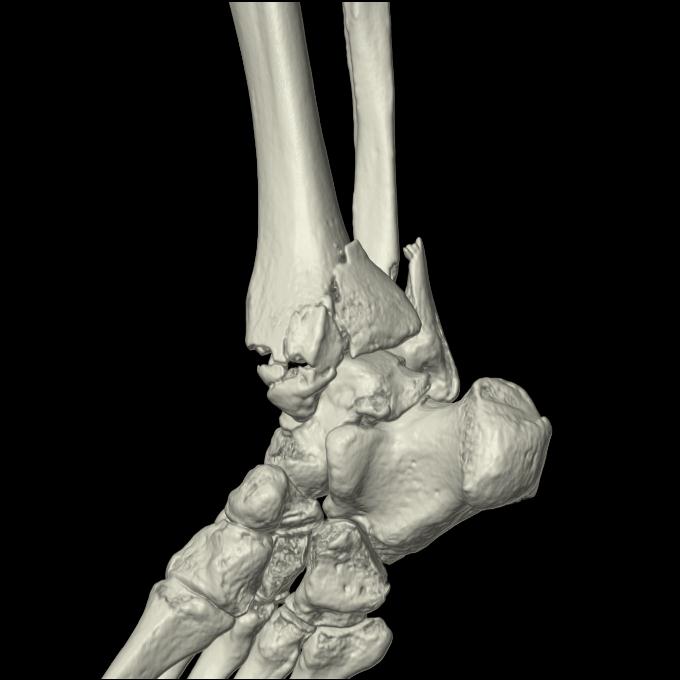

102755 1/4 2R 1/15 2R 右足関節 68歳女性 右三果脱臼骨折